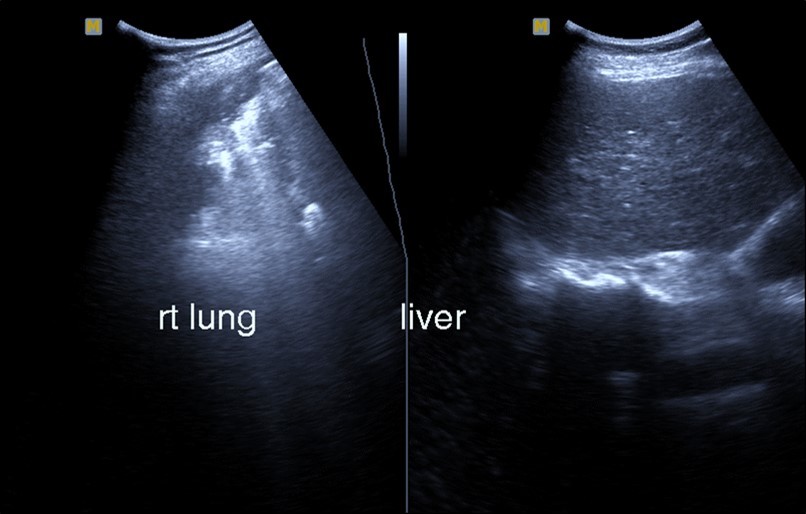

Abdominal ultrasound may revealed any of the followings:-Mild hepatomegaly with echogenic parenchyma and ascites in cases with hepatic impairment (Figure 4, Figure 5) ,thick walls of gall bladder with mildly dilated Common bile duct suggesting of biliary stasis and cholecystitis (Figure 6) .Abnormal renal echogenicity (Figure 7), suprarenal gland enlargements with heterogeneous texture ,splenic wedge shape area of hypoechogenicity ,thickened walls of bowel mainly the rectosigmoid region ,dilated bowel loops with free peritoneal fluid, and gases in the bowel wall with mesenteric and portal vein gases suggesting of bowel wall infarction13.

Figure 4.Real time ultrasound showing thickened wall of gall bladder (gb) with dilated Common bile duct (cbd) in patient with severe Covid-19.

Figure 5.Real time ultrasound showing mild hepatomegaly (li), ascites and thickened gall bladder wall(gb).